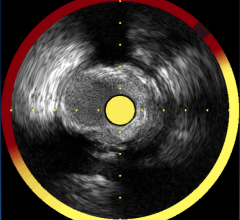

Intra-Vascular Ultrasound (IVUS)

This channel includes news and new technology innovations for Intra-Vascular Ultrasound (IVUS) used in interventional procedures.

Intravascular ultrasound (IVUS) is the workhorse intravascular imaging modality in cardiac cath labs. It is used to help ...